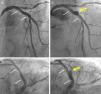

A 67-year-old man with hyperlipidemia was admitted for effort angina. Fifteen years before he had suffered an anterior myocardial infarction and a bare-metal stent (BMS) was implanted in the proximal left anterior descending coronary artery. Coronary angiography revealed proliferative ISR involving the proximal segments of the BMS but also extending 10 mm into the proximal vessel. OCT depicted severe neoatherosclerosis, with heavily calcified plaques, and a thin-cap fibroatheroma in the proximal segment. After aggressive lesion predilation the entire segment was covered with a 3.5 mm×23 mm BVS (Absorb, Abbott Vascular, CA), postdilated using a non-compliant balloon up to 24 atm, with an excellent final result (Figure 3A and B). OCT confirmed correct BVS expansion with a small residual coronary dissection behind the BVS and at its proximal border. The patient remained completely asymptomatic but a scheduled control angiogram at nine months revealed the development of a large CAA in the mid portion of the BVS (Figure 3C and D). OCT provided unique additional insights, revealing a CAA 11 mm in length with a maximum lumen area of 27.5 mm2. Notably, a striking displacement of the BVS struts was depicted, confirming the occurrence of BVS fracture (Figure 4).

(A and B) Angiographic result after implantation of a bioresorbable vascular scaffold (BVS) in the proximal left anterior descending coronary artery (small white arrows indicate the ends of the BVS); (C and D) at nine-month follow-up formation of a coronary artery aneurysm (yellow arrow) is demonstrated in the mid segment of the BVS.

(A-D) Optical coherence tomography images of the coronary artery aneurysm (CAA) (yellow arrow) with a maximum lumen area of 27.5 mm2. Some struts of the bioresorbable vascular scaffold appear covered but largely malapposed (A, thin yellow arrow), others were extensively displaced (B), whereas no struts could be detected in other areas of the CAA (C); (D) longitudinal view. * denotes wire artefact. LA: lumen area.